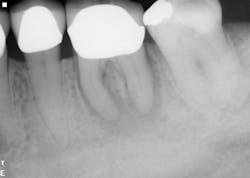

The second case involves a patient with tooth no. 19 having substantial furcation damage and moderate-sized apical periodontitis (figure 3).

Treatment included a two-visit approach, with two weeks in interim calcium hydroxide therapy.